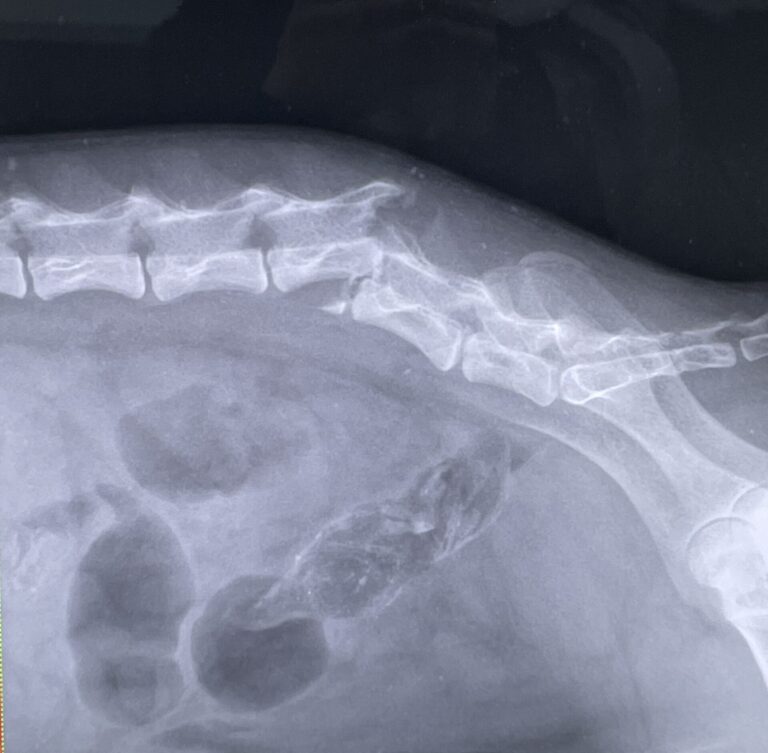

- 背骨骨折

- 両後ろ足不随